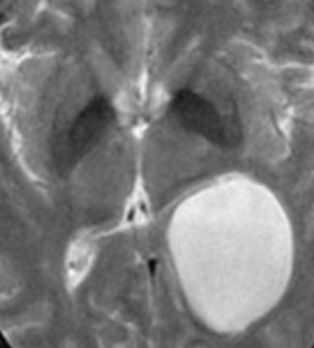

МРТ головного мозга. Т2-взвешенная корональная МРТ. Киста кармана Ратке.

Киста кармана Ратке представляет собой редко встречающееся образование из остатков эмбриональной эктодермы (щель Ратке), расположенное между долями гипофиза. Выявляется в любом возрасте, но чаще в 50-60 лет. Клинические проявления связаны с масс-эффектом. При головного мозга выявляется небольшая (3-5 мм) киста с четким контуром, без отека вокруг, однородная по структуре. Сигнал зависит от содержимого. При серозном содержимом сигнал типично жидкостный, при мукоидном киста светлая на Т1-взвешенных МРТ. В редких случаях киста достигает больших размеров и даже выходит за пределы седла. Стенка кисты иногда усиливается при контрастировании.

Киста кармана Ратке представляет собой редко встречающееся образование из остатков эмбриональной эктодермы (щель Ратке), расположенное между долями гипофиза. Выявляется в любом возрасте, но чаще в 50-60 лет. Клинические проявления связаны с масс-эффектом. При МРТ головного мозга выявляется небольшая (3-5мм) киста с четким контуром, без отека вокруг, однородная по структуре. Сигнал на МРТ головного мозга зависит от содержимого. При серозном содержимом сигнал типично жидкостный, при мукоидном киста светлая на Т1-взвешенных МРТ головного мозга. В 70-80% случаев внутри кисты выявляется неконирастирующийся узелок («пятно») - признак патогномоничный для кисты кармана Ратке. В редких случаях киста достигает больших размеров и даже выходит за пределы седла. Стенка кисты иногда усиливается при МРТ головного мозга с контрастированием. Дифференциальная диагностика при МРТ головного мозга должна проводиться с арахноидадьной и эпидермоидной кистами, тератомой, кистозной аденомой гипофиза и краниофарингиомой. Иногда при МРТ головного мозга киста кармана Ратке напоминает “пустое” турецкое седло. При маленьких размерах кисты ее на до дифференцировать на МРТ с микроаденомой гипофиза.